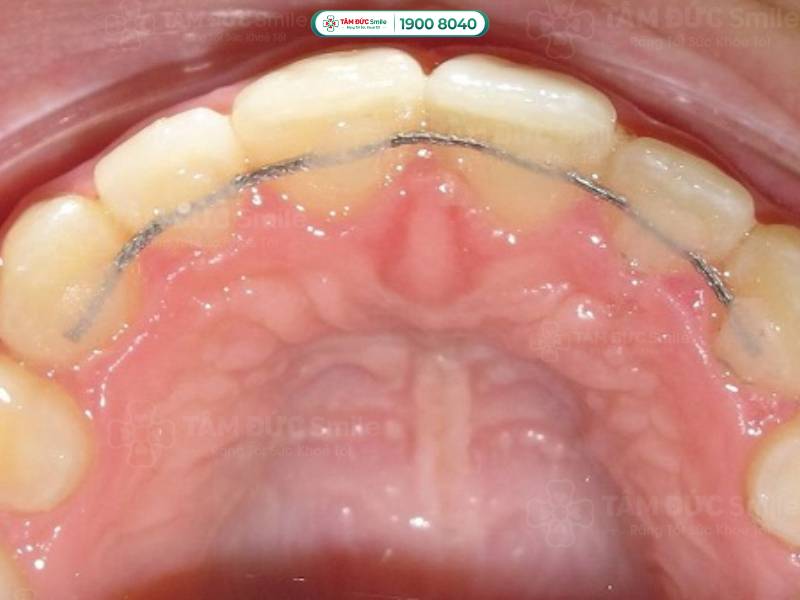

1.1.1. Hàm duy trì cố định

Hàm duy trì cố định được gắn cố định vào mặt trong của răng, thường là các răng cửa và răng nanh. Trước hết, bác sĩ sẽ làm sạch bề mặt răng, sau đó sử dụng keo nha khoa để gắn dây kim loại hoặc composite vào mặt sau của răng. Quá trình này không gây đau và hoàn thành nhanh chỉ trong một lần hẹn. Hàm duy trì cố định không thể tự tháo ra mà cần được thực hiện bởi bác sĩ để không ảnh hưởng đến vị trí của răng.

Hàm duy trì cố định được gắn cố định vào mặt trong của răng